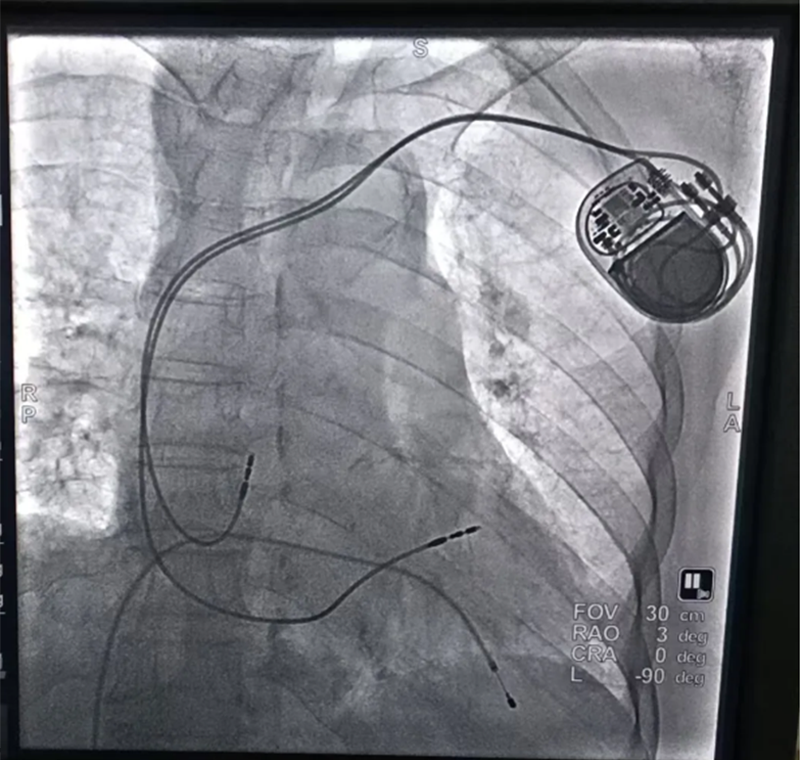

引人關(guān)注的87歲高齡王奶奶(化名),因"病態(tài)竇房結(jié)綜合征"命懸一線,心臟隨時(shí)可能停跳,傳統(tǒng)藥物治療無(wú)法解決問(wèn)題。面對(duì)患者復(fù)雜病情,馬建亮主任立即組織多學(xué)科(MDT)診療,針對(duì)高齡患者血管條件差、基礎(chǔ)病復(fù)雜等特點(diǎn),制定個(gè)體化手術(shù)方案,憑借其豐富的經(jīng)驗(yàn)和精湛醫(yī)術(shù),成功為其植入了雙腔永久起搏器。術(shù)后,起搏器運(yùn)行穩(wěn)定,王奶奶病情平穩(wěn),未再出現(xiàn)頭暈、短暫性意識(shí)喪失、胸悶等不適癥狀。

植入雙腔永久起搏器